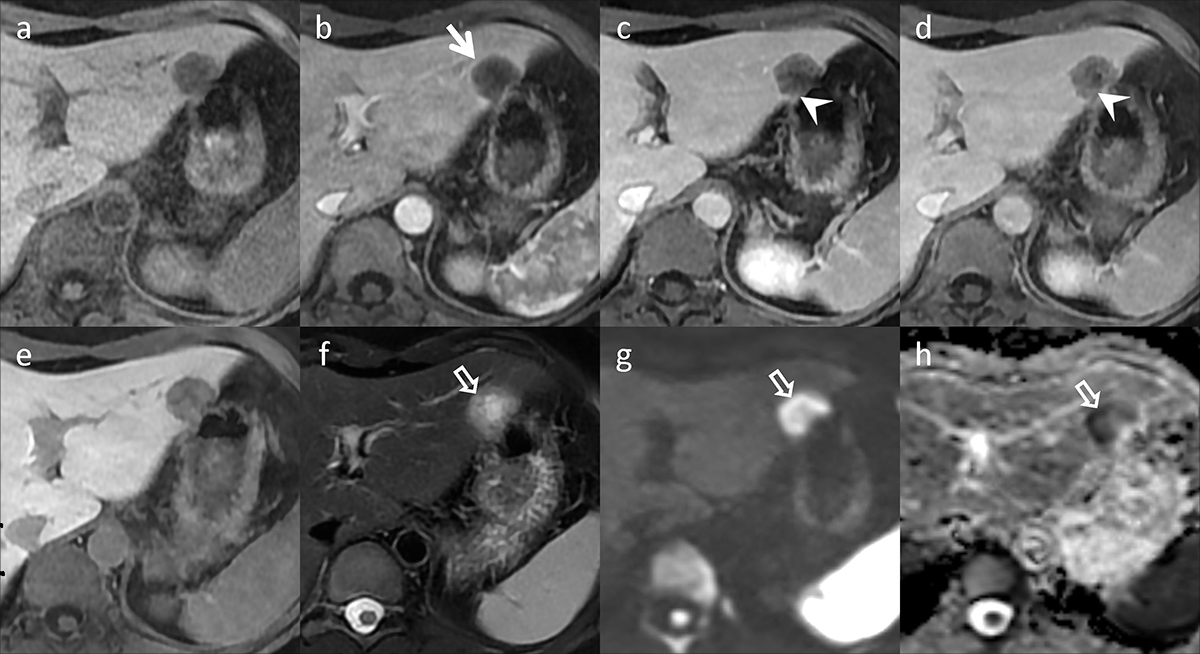

肝胆膵のCT・MRI | 本田浩, 角谷眞澄, 吉満研吾, 蒲田敏文, 入江裕之 |本 | 通販 | Amazon, 1. 診断のポイント|大腸癌肝転移の画像診断のUP to Date|GI-pedia|消化器癌治療の広場 GI cancer-net,

1. 診断のポイント|大腸癌肝転移の画像診断のUP to Date|GI-pedia|消化器癌治療の広場 GI cancer-net, 膵癌、EOB-MRIによる肝転移検索の重要性 | Search Radiology | 医療関係者向け情報,

膵癌、EOB-MRIによる肝転移検索の重要性 | Search Radiology | 医療関係者向け情報, 肝臓MRIにおける最新技術-技術解説 - GEヘルスケア・ジャパン株式会社 - inNavi Suite,